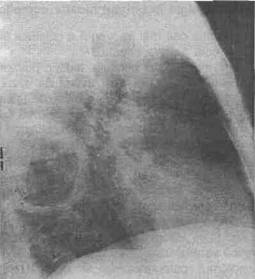

9. Tn chistui hidatic complicat examenul radiologic este caracteristic:

b. Tn eel evacuat: cavitatea intraparenchima-toasa bine delimitata cu semnul membranei ondu-late pe fundul lojei chistice (fig. 3, 4, 5).

c. Tn eel cu membrana Tncarcerata si lichid evacuat apare o opacitate omogena bine delimitata (vomica Tn anamneza).

Fig. 5 - Radiografie profil drept, imagine tipicS de chist hidatic evacuat cu mernbrana Tncarcerata pe fundul cavitatii - situata In lobul superior drept.